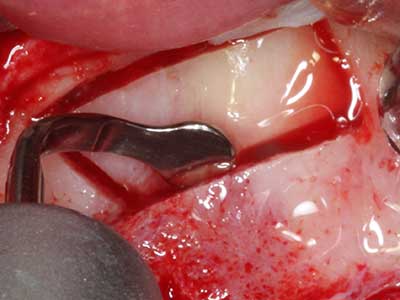

Bone tissue is not simply a mineral structure but also contains a substantial proportion of collagen fibres. This means it not only has good compressive strength but also a degree of flexibility, which can be taken advantage of when performing bone augmentations. In the classical expansion procedure using bone splitting, the atrophied alveolar ridge is split longitudinally and carefully expanded after reaching an adequate osteotomy depth (Fig. 13-16), ideally without substantial removal of the periosteum (Brugnami, Caiazzo et al. 2014, Stricker, Fleiner et al. 2014). Screw and plate systems with increasing expansion distance have proven effective in separating the two bone lamellae while remaining below the fracture threshold. In general, residual bone widths of at least 3–4 mm are required (Chiapasco, Zaniboni et al. 2006) to guarantee adequate flexibility and sufficient bone coverage of the future implants. If necessary, a vertical relief osteotomy on one or both sides can improve flexibility. A combination with additional augmentation techniques, particularly on the buccal side, has been described as an alternative to the classical technique.

The splitting procedure is particularly atraumatic and there is no significant loss of dimension when using piezosaws, and there are no significant differences between implants in split jaws and implants in an alveolar ridge without a bone deficit (Chiapasco, Zaniboni et al. 2006, Danza, Guidi et al. 2009). However, sufficient continuous irrigation is essential, particularly with locally restricted and deep splitting to prevent thermal stress in the apical osteotomy regions.